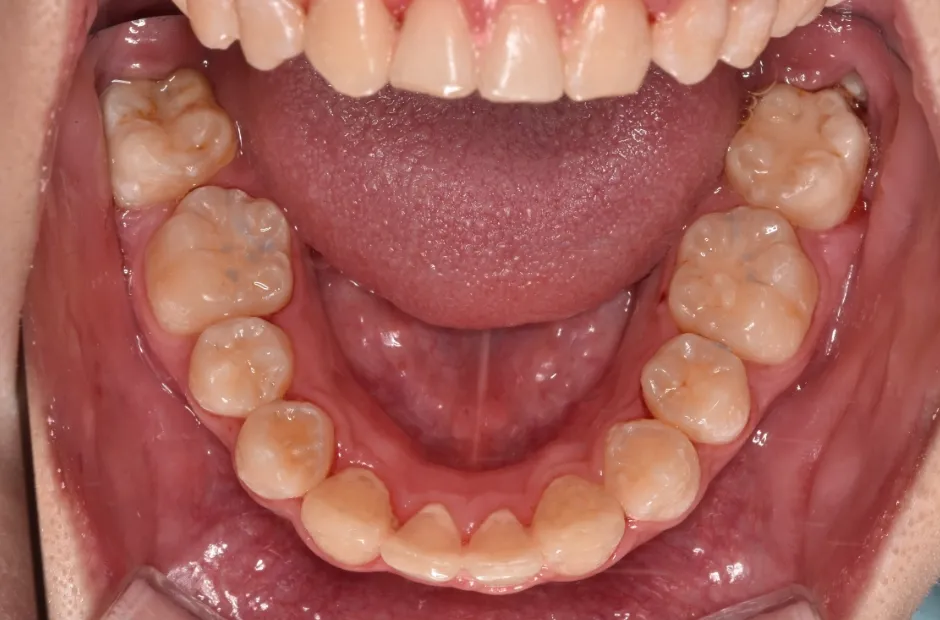

| 診断名・主訴 | 開咬 |

|---|---|

| 年齢・性別 | 23歳・女性 |

| 治療期間・回数 | 1年 12回 |

| 治療に用いた主な装置 | クワドヘリックス(QH)+タングガード → ロール付きリンガルアーチ |

| 抜歯部位 | 左右下8番 |

| 治療費 | 70万円(税抜) |

| リスク・副作用 | 装置による違和感・疼痛・歯肉退縮・歯根吸収・虫歯のリスクなど |

治療前

治療後